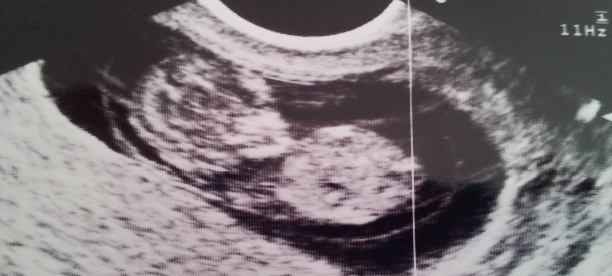

Its really early but isit possible to guess something, just for fun?:) Im around 11 weeks but it was measuring over 12 weeks.

Possibly boy?????

The nub. Are you hoping for a boy?